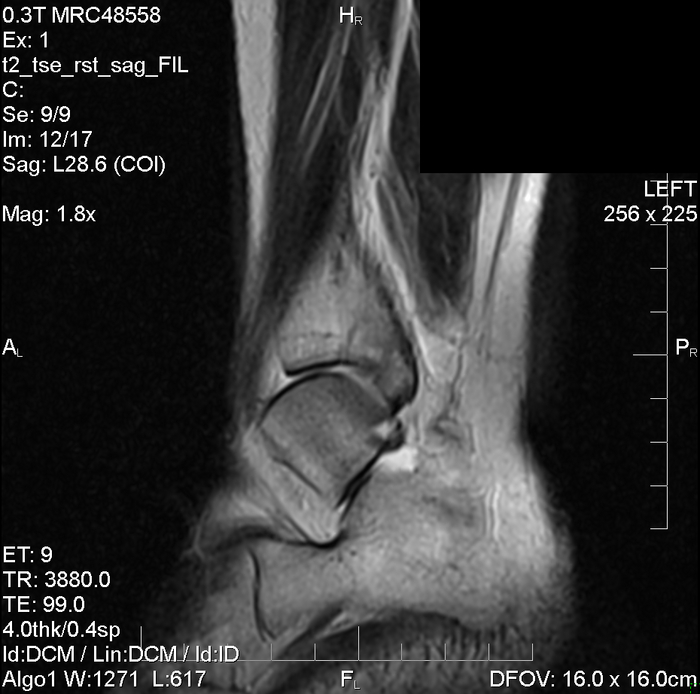

Жене 40 лет. Не спортсменка, но лишним весом не страдает. Вес 55 кг. Около полторы недели назад пожаловалась, что нога (левый голеностоп) болит и припухла. Она просто упомянула это "вскользь", не заостряя на этом внимание. У нее в дальних поездках часто оттекают ноги и это уже воспринимается как норма. Никаких травм, падений, даже подворотов ноги вроде не было. То есть нет какого-то момента который можно было бы считать моментом травмы. Надо отметить, что около двух недель назад купили ей абонемент в фитнес центр и соответственно неделю успели отходить - спортзал без фанатизма, бегать она не любит, на беговой дорожке в основном ходила, отдельно на тренажерах упражнения на ноги не делала. Потом сауна и бассейн. (Возможно это имеет значение)

Но спустя пару дней (с момента появления первых симптомов) мы уже начали беспокоится. Боль не проходит. При нажатии, даже легком - сильная боль. Опухоль тоже не проходит. После нажатия остается "ямочка", т.е. сразу не восстанавливается. Утром опухоль меньше, к вечеру больше, ну и к вечеру болит сильнее.

Фото левой и, для сравнения, правой стороны. С утра (когда опухоль меньше), тем не менее видно, что косточки не видно (простите за каламбур)

Обратились в больницу к терапевту. Терапевт дала направление на рентген (будет еще только через неделю), а к травматологу отказалась давать направление. Мы самостоятельно поехали на МРТ (платно). Вот результат.

Снимки МРТ заскринил и залил на дропмифайлз https://dropmefiles.com/3mYTL

Просмотр доступен и без скачивания. Один из снимков.

В этом медцентре консультация ортопеда-травматолога предусмотрена (даже бесплатная), но он в отпуске и ближайшая дата приема только 28 июля. В интернете при таких симптомах пугают, что если затянуть лечение, то вплоть до инвалидности можно дотянуть. Мы поехали в травму по Выборгскому району СПб. Там очередь просто огромная и судя по движению очереди, вернее по отсутствию движения, мы просто весь день бы отстояли бы в очереди и вероятно даже не попали бы на прием (сидячих мест мало и естественно заняты). Есть окошко платных услуг. Спросили можно платно и без очереди, там ответили, что да, но сначала надо в регистратуру, а потом уже в окно платных услуг. В общем когда дело дошло до оплаты, врач уже собрался домой. Короче решили поехать куда-нибудь еще платно, но оказывается, даже платно, приемы только на следующей неделе. Поэтому прошу помощи. 28 июля мы попадем на прием к врачу, но что можно начать делать уже сейчас?

Прочитав много разных текстов на эту тему мы купили Троксерутин гель и капсулы, и Нимесулид также гель и суспензию. Пробовали Диклафенак гель 5% - ноль эффекта, Терафлекс - тоже нет эффекта. В принципе хоть какой-то эффект только от Нимесулид суспензий, но это же просто обезбол. На данный момент продолжает пить Троксерутин и Нимесулид, и мазать этими же гелями. Собираемся наложить иммобилизирующую повязку в виде эластичного бинта.